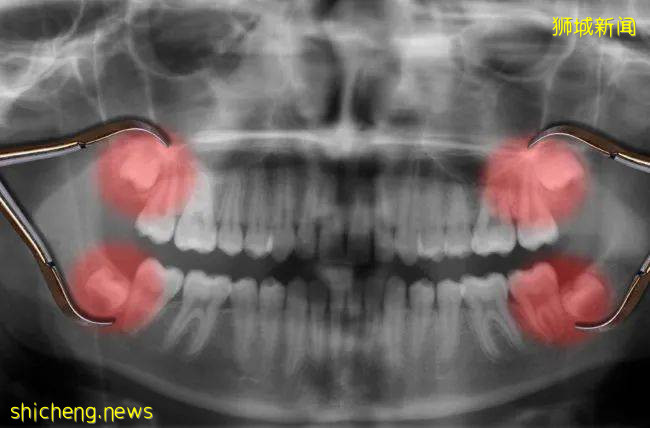

看诊、拿药、甚至做手术都有全民医保,拔个普通的智齿顶天也就花三四百块(五六十新币)。

在中国只需要五六十新币解决的智齿问题,来到新加坡,就需要五六百了。

这次因为疫情,不少人都不得不在新加坡看病和拔牙,大大出了一笔血……

一颗小小的牙齿都这么贵,老年人身体弱,很容易得病,他们的医疗费可想而知了……